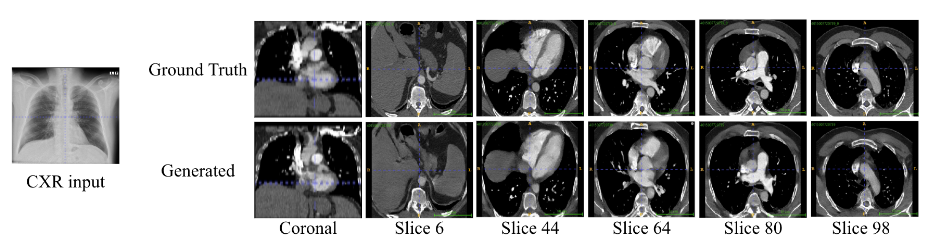

This study aims to introduce a novel method for reconstructing 3D CTPA images from 2D CXR images using generative models and diffusion models in deep learning. The developed model takes a chest X-ray as input and reconstructs the corresponding 3D anatomical structures, effectively enhancing the diagnostic value of standard 2D images. This approach not only improves the analysis and diagnosis of pulmonary diseases but also reduces the need for unnecessary CT scans and minimizes medical imaging costs.

An advanced AI architecture was employed in this project, trained on real CTPA and CXR datasets. The model is capable of reconstructing missing structural information from 2D images and presenting it in 3D format. The generated images can be used to assess a wide range of pulmonary conditions, including inflammations, structural abnormalities, unusual masses, infections, and other respiratory issues.

Initial results of the project indicate that the reconstructed images are highly accurate and capable of restoring critical structural information that is not visible in conventional radiographs. This method can serve as a complementary tool in medical imaging, paving the way for the development of innovative technologies in the diagnosis and analysis of pulmonary diseases. Furthermore, the approach can be extended to other areas of medical imaging, contributing to improved diagnostic accuracy, continuous patient monitoring, and more effective evaluation of treatment outcomes. The adoption of this technology across various medical fields has the potential to enhance image interpretation and support more informed clinical decision-making.